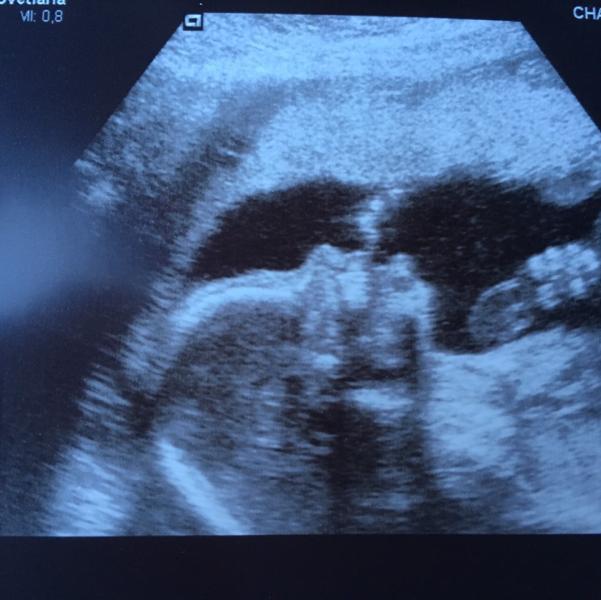

Тоже хочу поделиться приятной новостью. Были на втором скрининге, все у нас хорошо. Весим 377 грамм, пальцы уже во всю сосём. Носик нам на первом скрининге говорили маленький, вырос и все хорошо.Муж первый раз сегодня с нами был на узи. До этого с мамой ходила. Так вот он бедный толи от счастья, толи от неожиданности чуть в обморок не упал))) Зато теперь уже точно понимает, как выглядет пупырышка. Нам опять подтвердили мальчика. Очень переживали, потому что вчера у меня пошла кровь после генеральной уборки. Все хорошо видно капилляр лопнул.